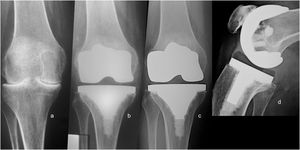

We found 27 radiolucent lines around 16 (22.22%) prosthetic components in 16 patients. All appeared during the first two postoperative years around of tibial component (Fig. 3). Ten patients presented one demarcated zone, 3 two zones, 2 three zones, and 1 four zones. All of them were <2mm and did not progress during follow-up. The frequency of RLL distribution is detailed in Fig. 4. No femoral component showed demarcation. No patients showed signs of osteolysis, migration of prosthetic components, or more than four areas with RLL.

The reoperation rate was 6.94% (n=5). All reoperations were performed within two years of the procedure (median 12 months; range 5–20). Four were due to prosthetic joint infections (PJI) and were successfully treated with a 2-stage revision. The remaining patient suffered an extensor apparatus rupture, as he fell from his height seven months after TKA and was successfully treated with a direct repair procedure. No mechanical failures were registered until the end of the study. Prosthetic survival at the end of the study was 94.4% (n=68).